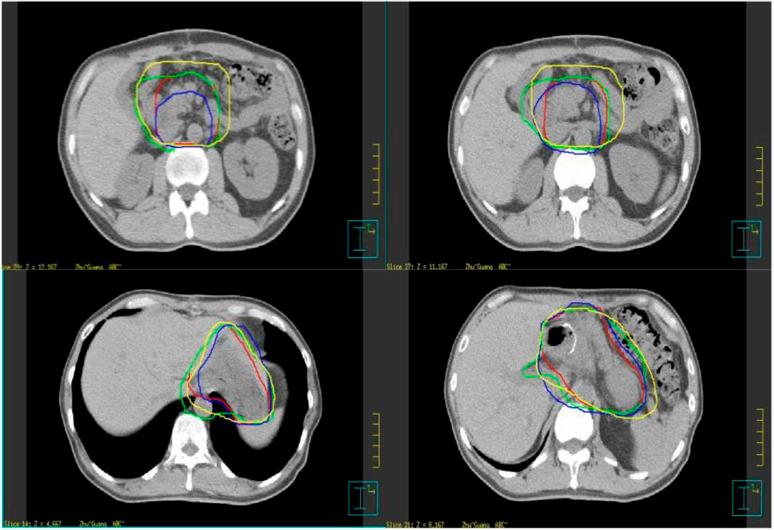

To investigate interobserver and inter-CT variations in using the active breath co-ordinate technique in the determination of clinical tumour volume (CTV) and normal organs in post-operative gastric cancer radiotherapy.

Ten gastric cancer patients were enrolled in our study, and four radiation oncologists independently determined the CTVs and organs at risk based on the CT simulation data. To determine interobserver and inter-CT variation, we evaluated the maximum dimensions, derived volume and distance between the centres of mass (CMs) of the CTVs. We assessed the reliability in CTV determination among the observers by conformity index (CI).

The average volumes ± standard deviation (cm(3)) of the CTV, liver, left kidney and right kidney were 674 ± 138 (range, 332-969), 1000 ± 138 (range, 714-1320), 149 ± 13 (range, 104-183) and 141 ± 21 (range, 110-186) cm(3), respectively. The average inter-CT distances between the CMs of the CTV, liver, left kidney and right kidney were 0.40, 0.56, 0.65 and 0.6 cm, respectively; the interobserver values were 0.98, 0.53, 0.16 and 0.15 cm, respectively.

In the volume size of CTV for post-operative gastric cancer, there were significant variations among multiple observers, whereas there was no variation between different CTs. The slices in which variations more likely occur were the slices of the lower verge of the hilum of the spleen and porta hepatis, then the paraoesophageal lymph nodes region and abdominal aorta, and the inferior vena cava, and the variation in the craniocaudal orientation from the interobserver was more predominant than that from inter-CT.